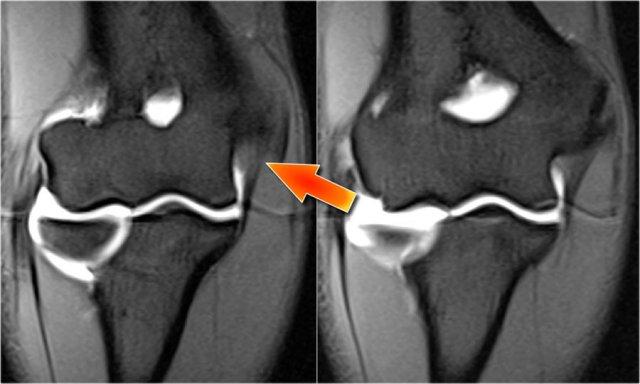

Ở đây chúng ta thấy hai hình ảnh mặt phẳng coronal liên tiếp của dây chằng bên trụ (UCL).

Bình thường có thể thấy một số tín hiệu cao ở phần gần (mũi tên).

Hãy chú ý cách nó bám chắc vào củ sublime và so sánh với các hình ảnh tiếp theo.

UCL tear

Hãy nhớ rằng dây chằng UCL phải bám rất chắc vào củ sublime.

Trong trường hợp này thì không như vậy, vì vậy ngay cả trên hai hình ảnh này bạn có thể nhận thấy rằng có một rách hoàn toàn.

Lưu ý rằng có một số phù tủy xương ở củ sublime.